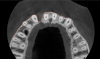

Tomographic images revealed a large tridimensional defect, with vertical and horizontal loss of bone extending to the apical third of teeth Nos. 6 and 8. Additionally, a buccal bone dehiscence was evident on tooth No. 5, and thin labial plates secondary to the orthodontic movement were present in several areas (Figure 3 and Figure 4).

Fig 3. Tomographic images revealed a tridimensional defect extending to the apical third of teeth Nos. 6 and 8, a buccal bone dehiscence on tooth No. 5, and associated thin labial plates.

Figure 3

Fig 4. Tomographic images revealed a tridimensional defect extending to the apical third of teeth Nos. 6 and 8, a buccal bone dehiscence on tooth No. 5, and associated thin labial plates.

Figure 4